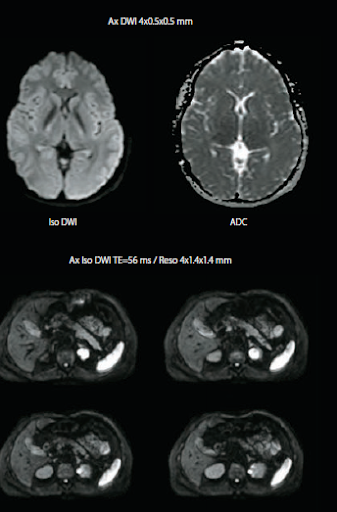

Quick Star снижает количество артефактов из-за движения, что особенно важно для исследования пациентов, которые не могут задержать дыхание и особенно для проведения МРТ-исследования печени.

МРТ без контрастирования

В последнее время все больше внимания уделяется изучению потенциальных рисков, связанных с контрастными веществами на основе гадолиния. Технологии, позволяющие проводить полноценное МРТ-исследования без контраста, сводят к минимуму риск для пациентов с чувствительностью к веществам для контрастирования, при этом не снижая качество диагностики.

Диффузионно-взвешенное изображение с технологией PUREGradient

- Более чем в 2 раза меньше времени на сканирование. Исследование мозга за 5 минут